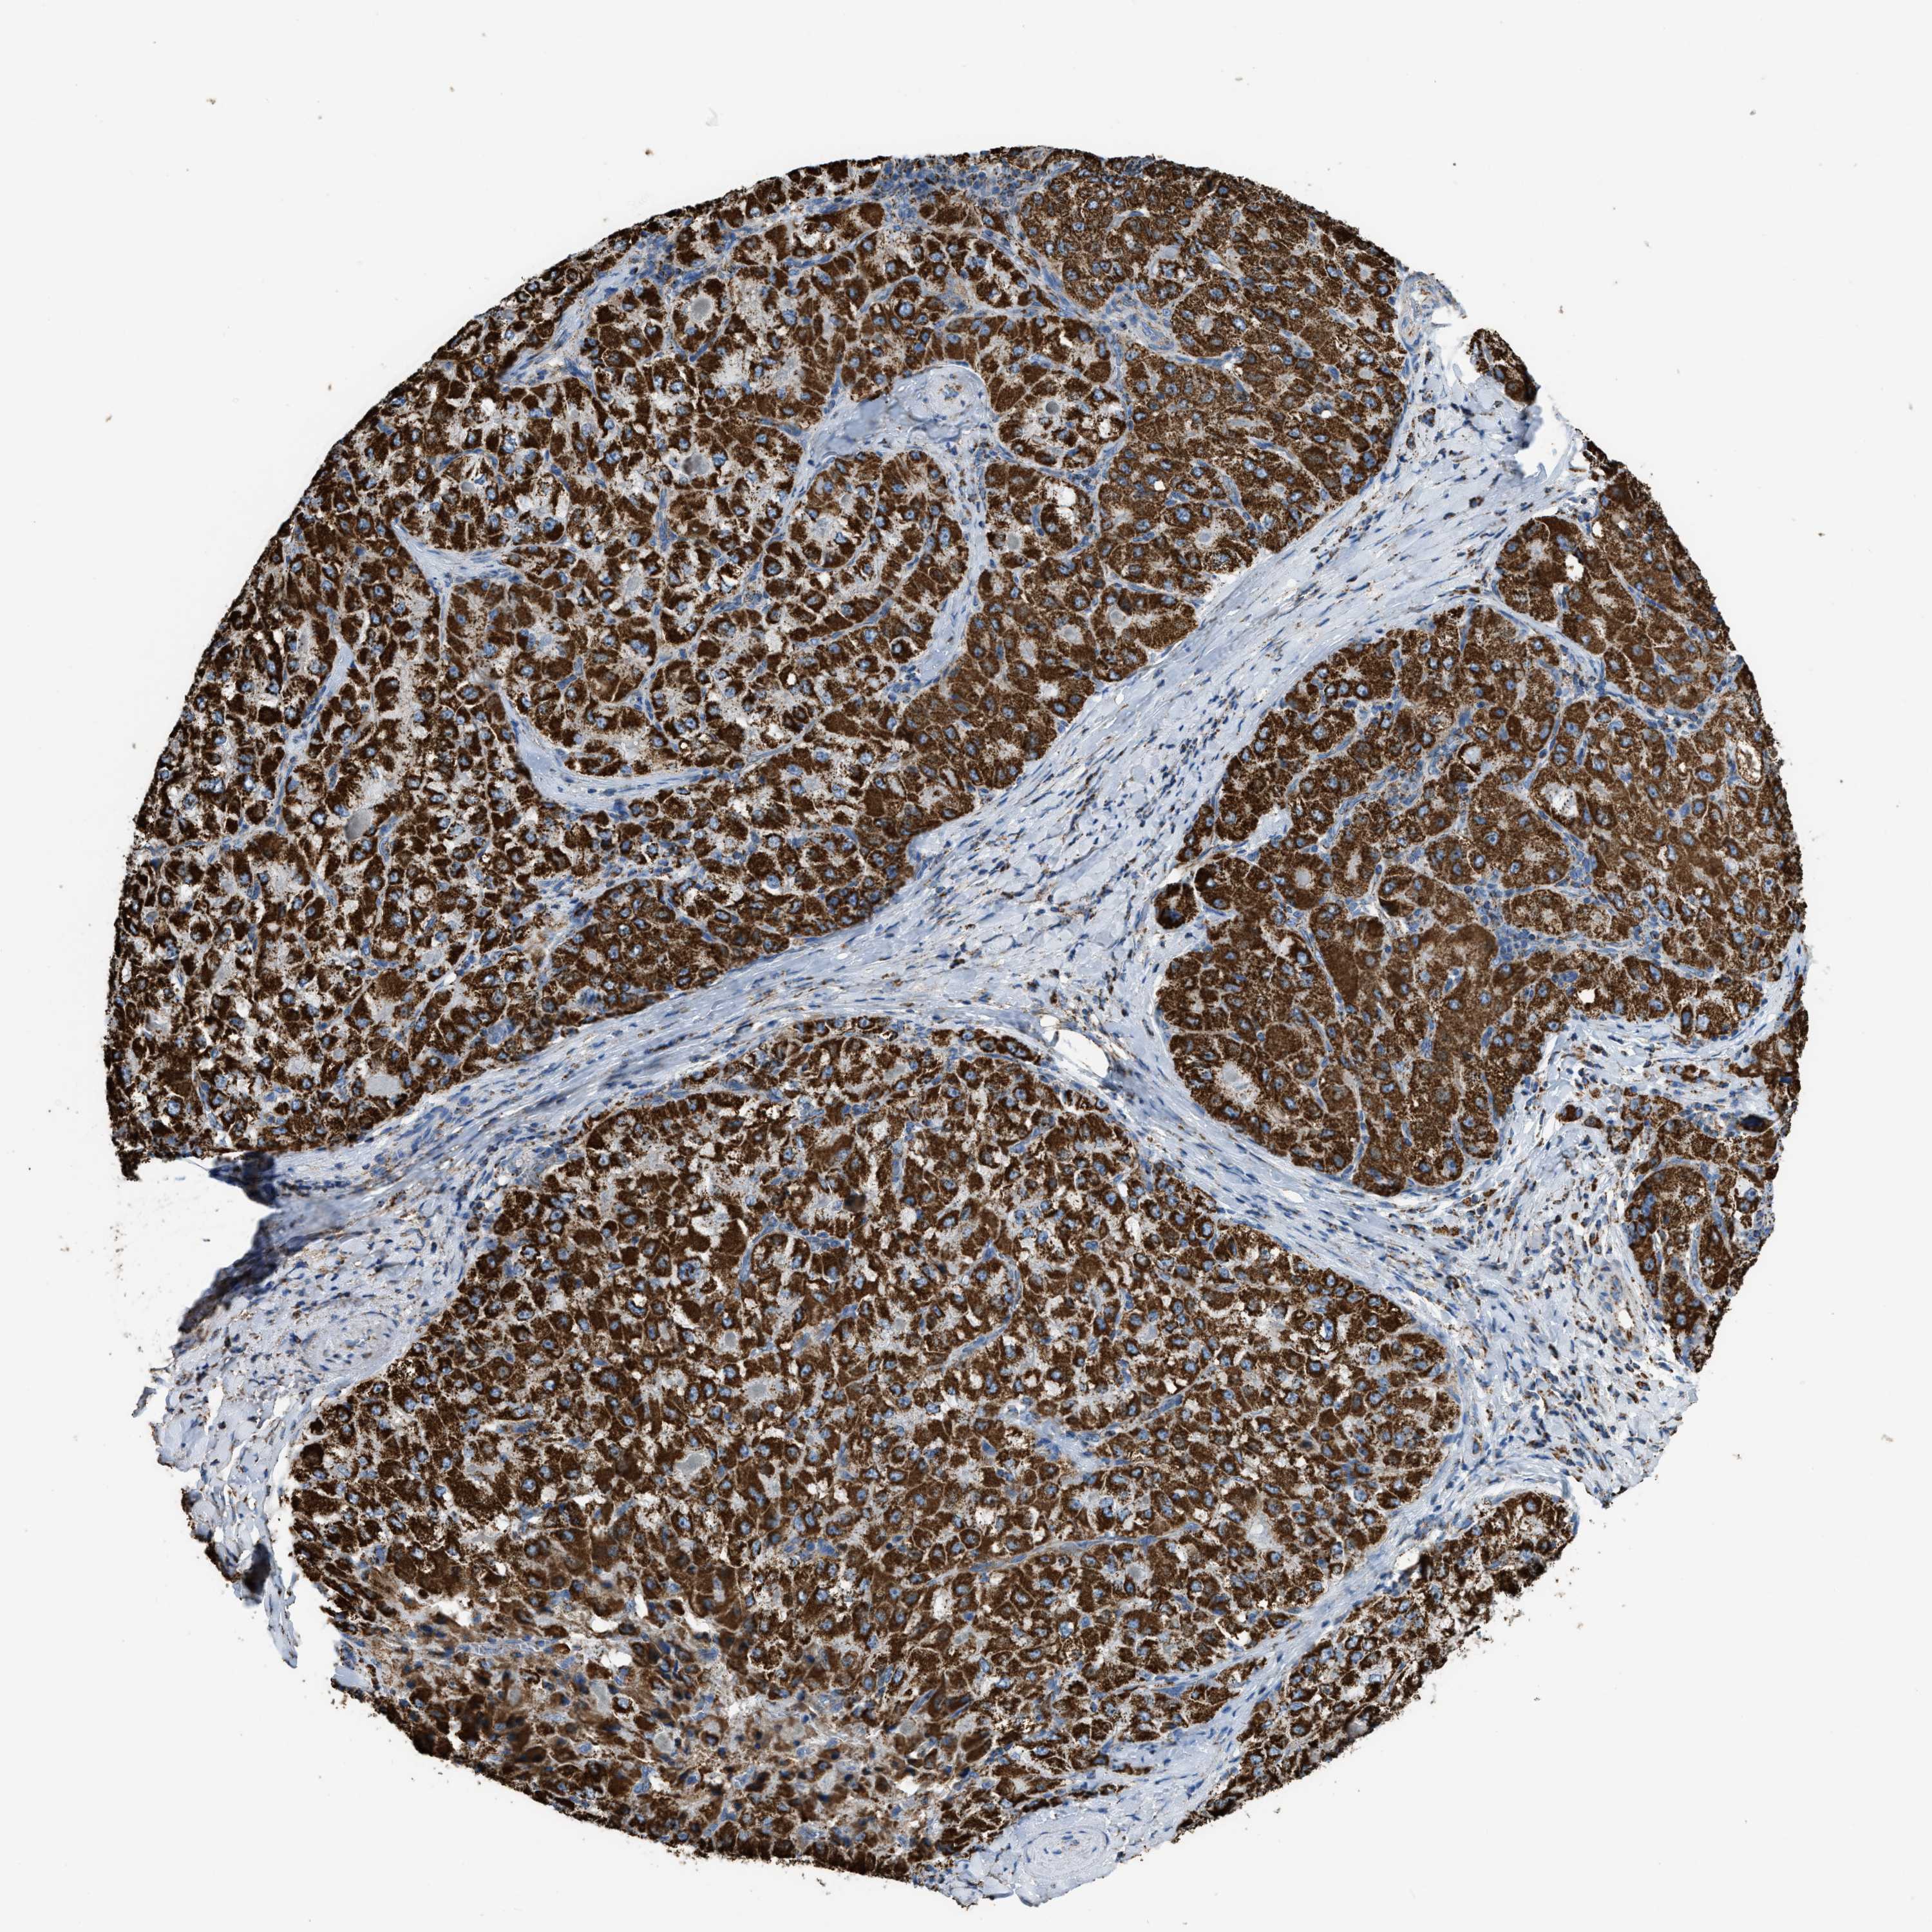

LIVER CANCER - Protein expressioni

A mouse-over function shows sample information and annotation data. Click on an image to view it in a full screen mode. Samples can be filtered based on level of antibody staining by selecting one or several of the following categories: high, medium, low and not detected. The assay and annotation is described here.

Note that samples used for immunohistochemistry by the Human Protein Atlas do not correspond to samples in the TCGA dataset.

Antibody stainingi

Antibody staining in the annotated cell types in the current human tissue is reported as not detected, low, medium, or high, based on conventional immunohistochemistry profiling in selected tissues. This score is based on the combination of the staining intensity and fraction of stained cells.

Each image is clickable and will lead to virtual microscopy that enables deeper exploration of all samples and also displays staining intensity scores, fraction scores and subcellular localization as well as patient and tissue information for each sample.

Antibody HPA018910

Antibody HPA018921

Antibody HPA018923

Staining

High

Medium

Low

Not detected

Intensity

Strong

Moderate

Weak

Negative

Quantity

>75%

75%-25%

<25%

None

Location

Nuclear

Cytoplasmic/membranous

Cytoplasmic/membranous,nuclear

Cholangiocarcinoma

Carcinoma, Hepatocellular, NOS